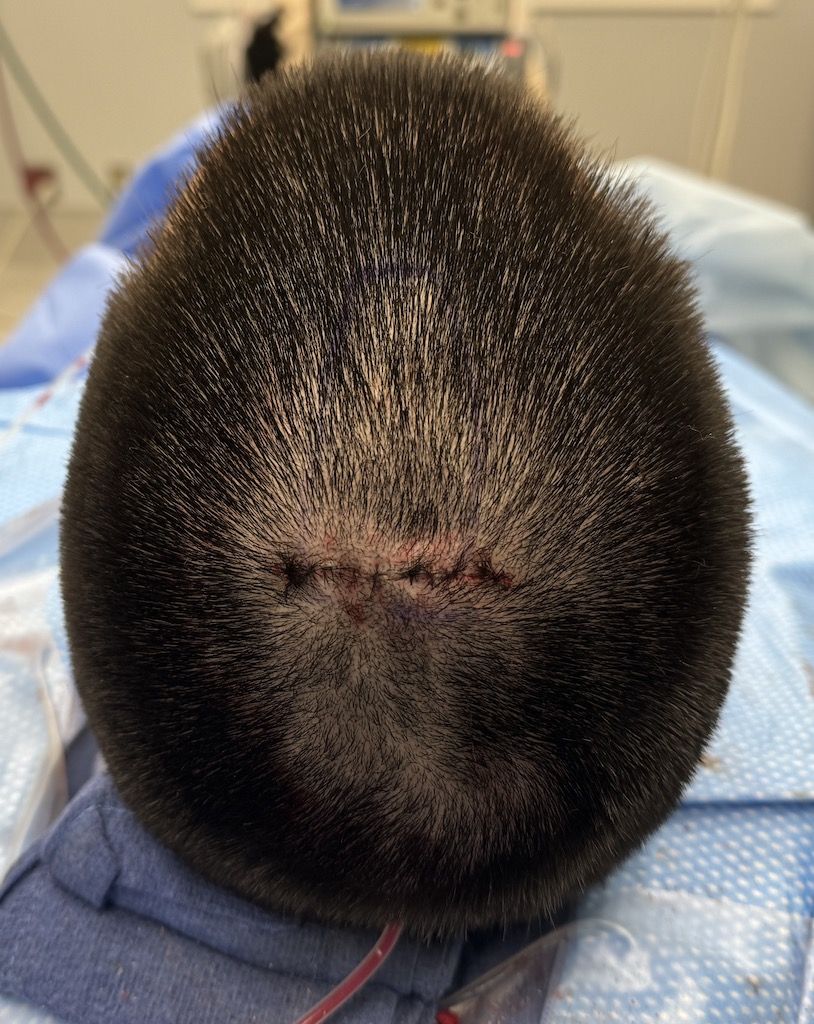

Desire for removal of occipital knob on back of skull.

Occipital knob skull reduction done through a small 3cm overlying skin incision.